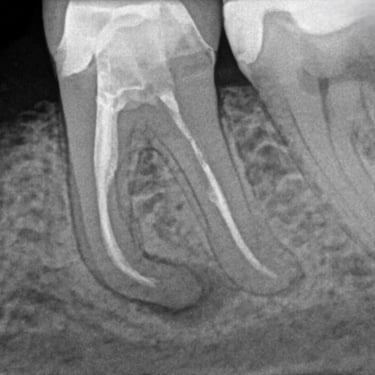

Fractura Radicular Vertical

Una fractura radicular vertical es una fisura que se extiende a lo largo de la raíz del diente, a menudo causada por un trauma o una presión excesiva.

Los pacientes suelen sentir dolor al morder y pueden notar hinchazón.

La fractura generalmente requiere la extracción del diente, ya que es difícil de reparar. Es crucial tratarla rápidamente para evitar infecciones.

Perforación Radicular

Una perforación radicular es una abertura anormal en la raíz del diente, generalmente debido a un procedimiento dental fallido o una caries profunda.

Los pacientes pueden sentir dolor y notar hinchazón en la encía.

El tratamiento incluye la reparación de la perforación y el tratamiento de conducto. Es crucial reparar la perforación para evitar una infección.